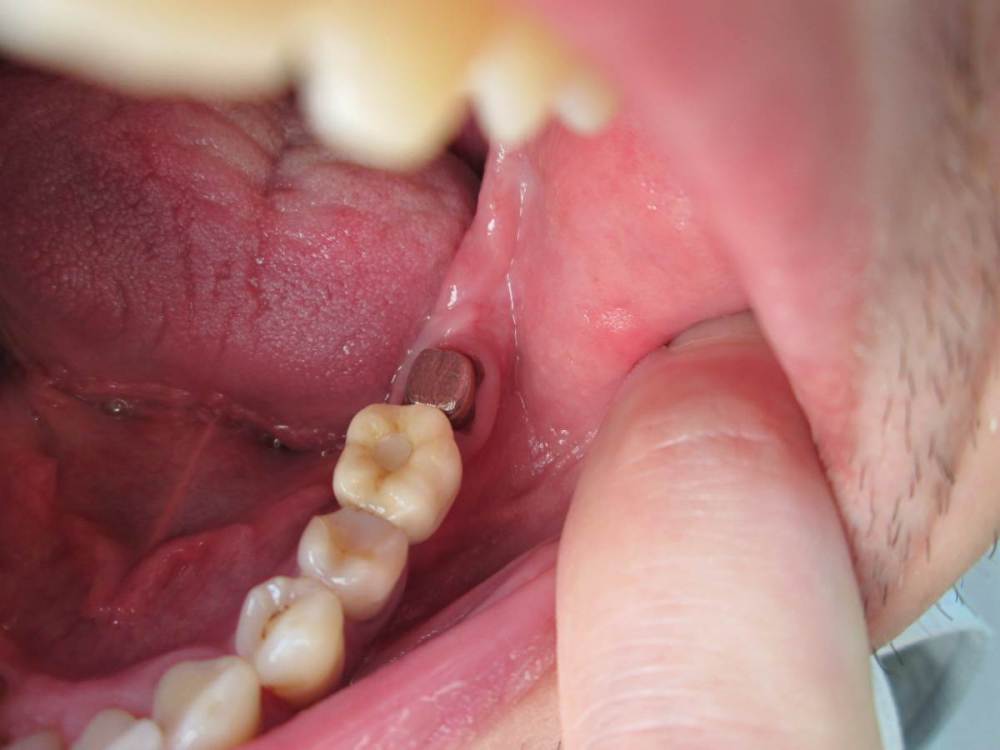

Jonik Опубликовано 29 июня, 2022 Поделиться Опубликовано 29 июня, 2022 Здравствуйте! Поставили коронку на временный цемент, недавно она отвалилась, нужно идти фиксировать на постоянный цемент но коронка мне не совсем нравится. Слой керамики в некоторых местах выходит за пределы металлического основания. Где то слой керамики заглажен к металлу, а где то имеет утолщение. Можно ли фиксировать такую коронку или переделывать. Если поставить эту коронку, могут ли потом возникнуть проблемы с гигиеной или с десной? Ссылка на комментарий

Jonik Опубликовано 30 июня, 2022 Автор Поделиться Опубликовано 30 июня, 2022 31 минуту назад, Doc сказал: Тут весь вопрос в том, что это было. Если керамическое плечо, то это нормально и даже когда-то приветствовалось. Если же техник просто металл не дотянул, а потом решил керамикой доляпать, то это совсем другой вопрос. Как во рту сидит? По десне все хорошо, либо над, либо глубоко под? Где уступ? Коронка точно без плеча. Когда была первая примерка врач отправил коронку на корректировку, сказал что нужно поправить немного. Может как раз это и был недотянутый метал. Как во рту сидит мне не нравится, местами под десну заходит. Ближе к уступу коронка кажется массивной, имеет утолщение возле десны, как бы наплывает на десну, приходится промывать ирригатором. Ссылка на комментарий